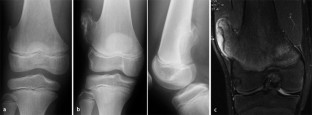

Abb. 2